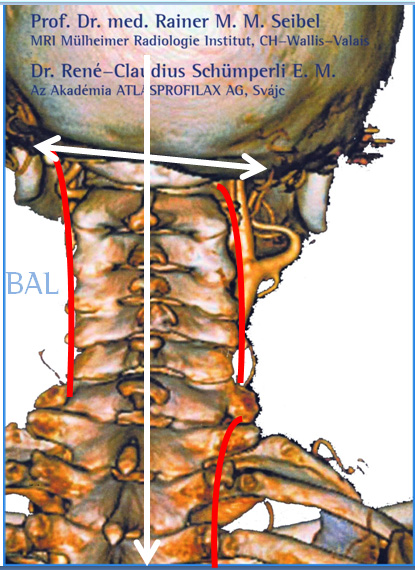

Súlyos testi és lelki panaszainak megoldását keresve René Claudius SCHÜMPERLI az 1993-1996-ig tartó intenzív kutatásai során rádöbbent arra, hogy a koponya-atlasz ízületben az Atlasz (első nyakcsigolya) szinte minden embernél ficamszerűen elfordult állapotban van. Megállapította azt is, hogy az atlasz elfordulását változó mértékű elbillenés is kíséri. Tehát a koponya alátámasztottsága nem vízszintes, és változó mértékű és súlyosságú egyensúlytalanság lép fel. A […]]]>

Súlyos testi és lelki panaszainak megoldását keresve René Claudius SCHÜMPERLI az 1993-1996-ig tartó intenzív kutatásai során rádöbbent arra, hogy a koponya-atlasz ízületben az Atlasz (első nyakcsigolya) szinte minden embernél ficamszerűen elfordult állapotban van. Megállapította azt is, hogy az atlasz elfordulását változó mértékű elbillenés is kíséri. Tehát a koponya alátámasztottsága nem vízszintes, és változó mértékű és súlyosságú egyensúlytalanság lép fel. A […]]]>

Elbillent Atlasz A Magyar AtlasPROfilax Társaság hivatalos honlapja és a specialisták megtekinthetők a http://atlaszprofilax.com honlapon. A világ 30 országában mintegy 350 specialista jogosult alkalmazni ezt a különleges eljárást, amit a svájci René Claudius SCHÜMPERLI dolgozott ki 1993-1996-ig. Az ATLASPROFILAX® egy speciális lágyrész wellness-masszázs kezelés, ami az első nyakcsigolya normális pozícióba való visszatérését teszi lehetővé. A feltaláló a világon elsőként észlelte […]]]>

Elbillent Atlasz A Magyar AtlasPROfilax Társaság hivatalos honlapja és a specialisták megtekinthetők a http://atlaszprofilax.com honlapon. A világ 30 országában mintegy 350 specialista jogosult alkalmazni ezt a különleges eljárást, amit a svájci René Claudius SCHÜMPERLI dolgozott ki 1993-1996-ig. Az ATLASPROFILAX® egy speciális lágyrész wellness-masszázs kezelés, ami az első nyakcsigolya normális pozícióba való visszatérését teszi lehetővé. A feltaláló a világon elsőként észlelte […]]]>